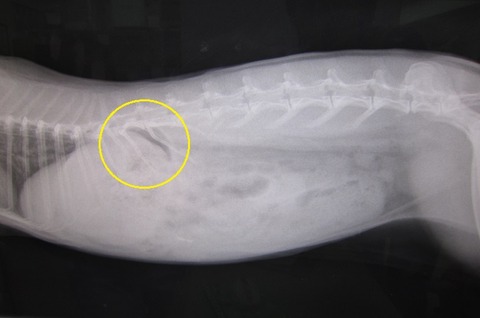

先生とも合致してたのだが、この黄色印をつけてるホッペの部分から、

ほとんどが出てくる感じ。

下や他の部分のかさぶたを取って押し出そうとしても、

印をつけてるところから出る、みたいな…